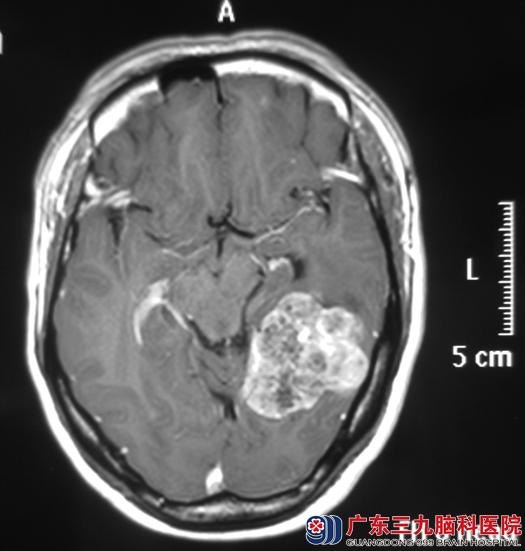

广东三九脑科医院头颅MR检查提示左侧颞枕部一不规则分叶病灶,大小约45.8mm×46.9mm×29.4mm。综合神经外科鲁明主任凭借多年的临床经验初步判断是脑膜瘤的可能性大。

完善检查后,由鲁明主任主刀,在全麻下行左侧颞枕部小脑幕上脑膜瘤切除术,术中显微镜下见淡红色肿瘤组织,质软、血供丰富、边界清楚,肿瘤基底位于小脑幕上,分块完整切除。术后病理结果为:过渡型脑膜瘤(WHO I级)伴钙化。

手术前